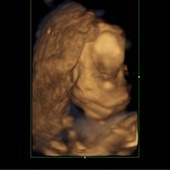

看到宝宝超激动

妇保院的医生其实一直强调作为排畸项目来说,三维与四维没什么实质性的区别,虽然有家属可以现场看超声检查情况,但宝宝像谁,长得什么样其实都是准爸准妈在脑袋里构思瞎想的,因为毕竟没有见到出生的宝宝没有可以对比的参照物,是很难去描绘像与不像甚至是像什么的问题。但妇保院